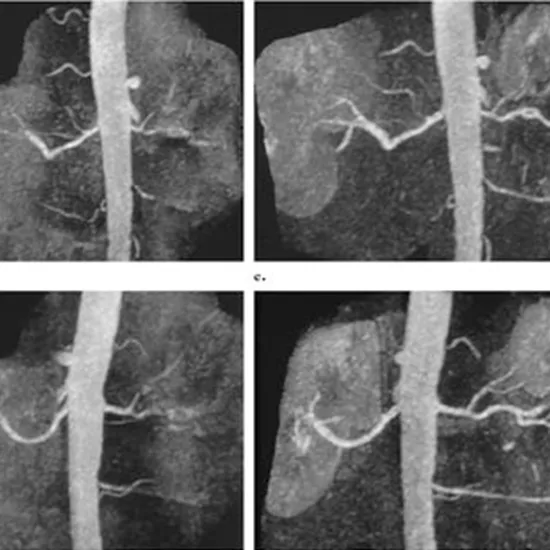

MR Angiography Aorta with Contrast is the process of an imaging test that accurately shows aortic dissection. It offers a high speed of postprocessing and ease as well. In addition, it does not make use of any ionising radiation.

MR Angiography Aorta with Contrast helps produce 3-dimensional images of the aortic dissection. It is done for treatment planning and accurate diagnosis. It provides accurate and fast results in comparison to other ways.